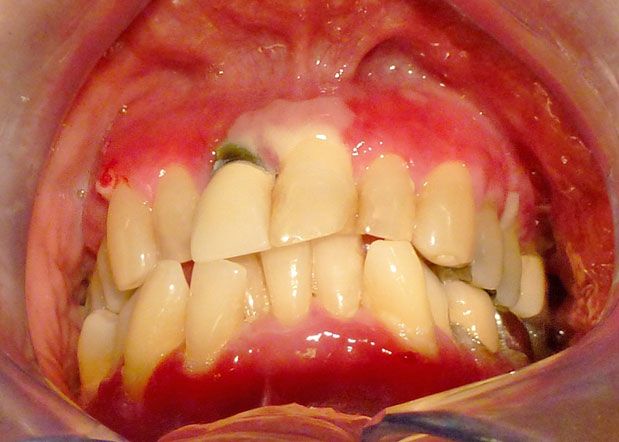

Figure 2.

Moderate to severe erythema of gingiva.